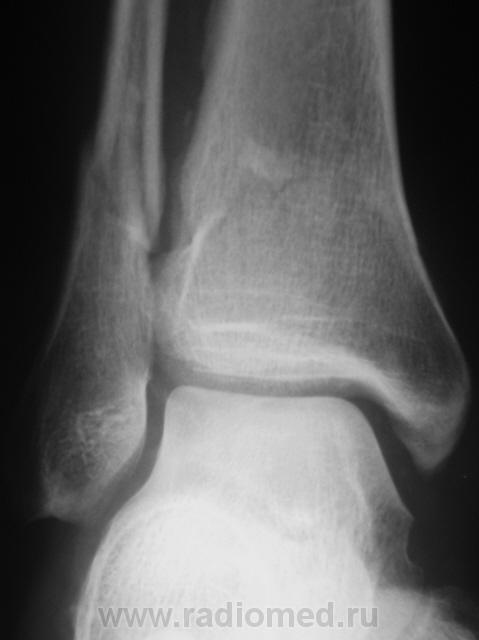

Травма. Перелом. Произведена рентгенография в стандартных проекциях в ургентном порядке.

Внутрисуставной перелом заднего края дист.эпиметафиза б/б кости или перелом "третьей лодыжки", со смещением фрагмента по ширине кзади,по длине - кверху до 5 мм и под углом, открытым кзади, с подвывихом стопы кзади, оскольчатый перелом н/3 диафиза м/б кости со смещением дистального фрагмента по ширине, по длине и угловым /открытым кзади/.

ну и еще перелом внутренней лодыжки